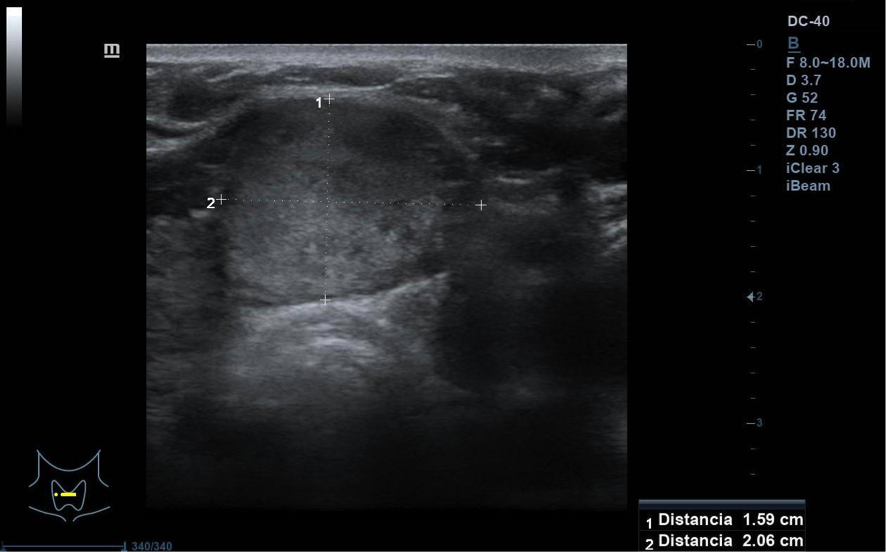

Se visualiza nódulo tiroideo en la unión del istmo con lóbulo tiroideo derecho, sólido, con cierta heterogenicidad, halo grueso anecogénico. Una zona del borde irregular, con mayor señal Doppler y de crecimiento excéntrico. Mide de diámetro máximo 25 x 20 mm. Adenopatías no patológicas.

La paciente fue remitida a Endocrinología para valoración de nódulo tiroideo de 2,5 cm, se solicitó ecografía para PAAF que objetivó nódulo TIRADS-4, PAAF con categoría Bethesda IV: neoplasia folicular con signos de células de Hürtle. Técnica IHQ de Calcitonina negativa. Se envía a Cirugía general y Digestivo para programar cirugía. Se realiza istmectomía y la AP revela que se trata de un tumor folicular de potencial maligno incierto, márgenes libres. Estudio genético con mutación del gen TERT.